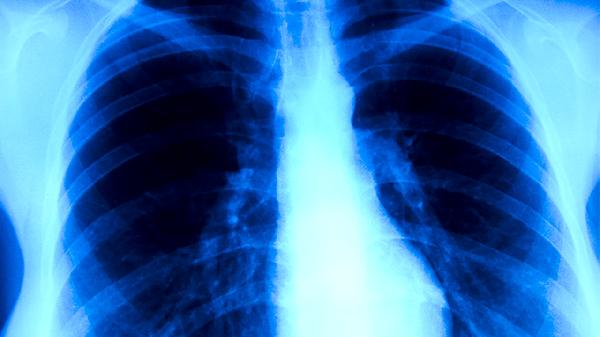

间质性肺炎患者应严格遵医嘱进行规范治疗,中药使用需在呼吸科和中医科医师共同指导下进行。日常需避免接触粉尘和冷空气刺激,保证优质蛋白摄入以维持营养状态,进行适度呼吸功能锻炼。出现气促加重或发热时应及时复诊,不可自行调整药物或依赖单一疗法。定期进行肺功能检查和胸部影像学评估对监测病情变化至关重要。